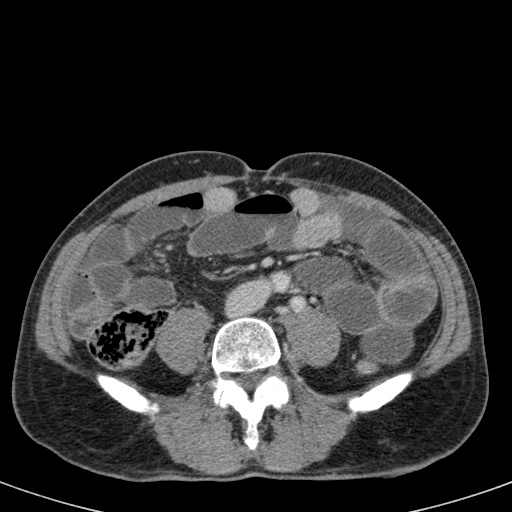

Ca lâm sàng bên trái cho thấy một bệnh nhân khác bị tắc ruột dạng quai kín.

Mặc dù các mạch máu ngấm thuốc tốt, nhưng dường như thành ruột không ngấm thuốc.

Các dấu hiệu thiếu máu cục bộ khác trong ca này bao gồm phù nề mạc treo và dày thành ruột.

Ruột bị nhồi máu được phát hiện trong quá trình phẫu thuật.

Nếu quai kín dài hơn và định hướng vuông góc với mặt phẳng cắt, chúng ta sẽ thấy một cụm quai ruột như trong ca lâm sàng bên trái.

Đôi khi điều này khó nhận biết chỉ trên các lát cắt ngang và các tái tạo mặt phẳng coronal hoặc sagittal có thể hữu ích.

Trong ca này, cũng có phù nề mạc treo và cổ